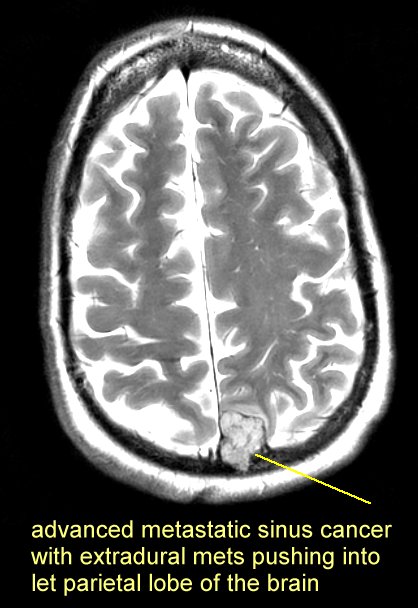

brain mets that eroded through the skull here and an extradural met pushing into the brain here